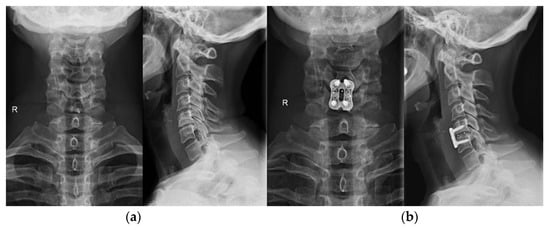

5.1. Spine

- Callanan, G.; Radcliff, K.E. Cervical Total Disc Replacement: Long-Term Outcomes. Update Motion Preserv. Technol. 2021, 32, 461–472. [Google Scholar] [CrossRef]